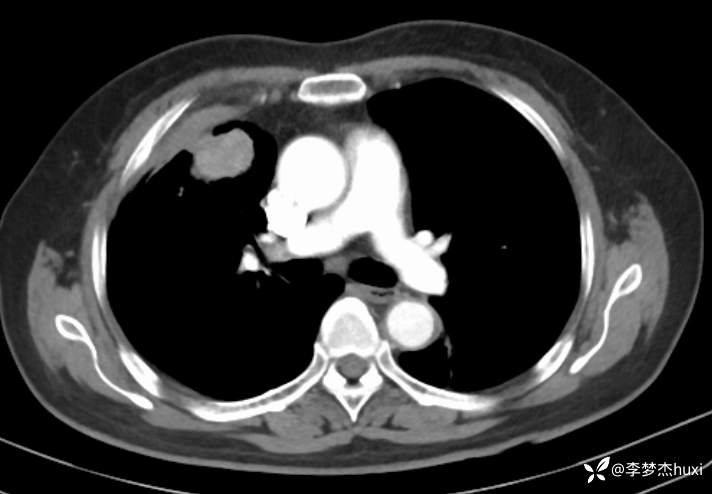

辅助检查:胸部CT:右肺占位?炎症?双肺炎性变,左肺下叶陈旧性病变,双肺纹理增多,主动脉及冠状动脉钙化,双侧胸膜局部增厚,胆囊结石,多发肝囊肿?请结合超声。

临床诊断:肺占位